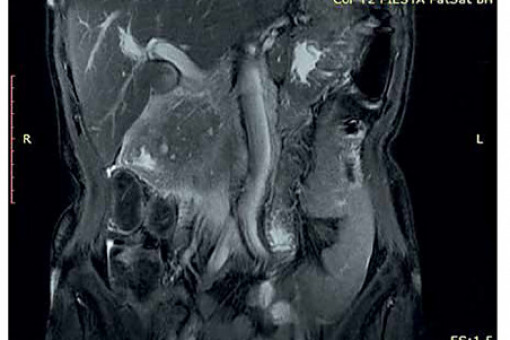

Z powodu niejednoznacznych wyników badań obrazowych pacjentce zaproponowano badanie metodą rezonansu magnetycznego z dożylnym podaniem środka kontrastowego (Gadovist) z zastosowaniem sekwencji FOCUS DWI do zobrazowania zmian w trzustce. W tym badaniu w obrębie głowy trzustki widoczna była niejednorodna masa wielkości 76 × 50 × 53 mm, w fazie T1 hipointensywna, ulegająca nieco słabszemu wzmocnieniu pokontrastowemu w porównaniu z pozostałym miąższem trzustki, wykazująca niejednorodne ograniczenie dyfuzji (ryc. 3–6).